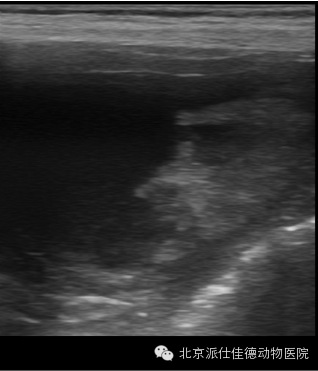

14.有些动物突然出现贫血,也没有发生外伤,腹围突然增大,经检查发现内脏大出血,最常见的是血管瘤破裂,如脾脏肿瘤破溃、肝脏肿瘤破溃、主动脉夹层瘤破裂等等。